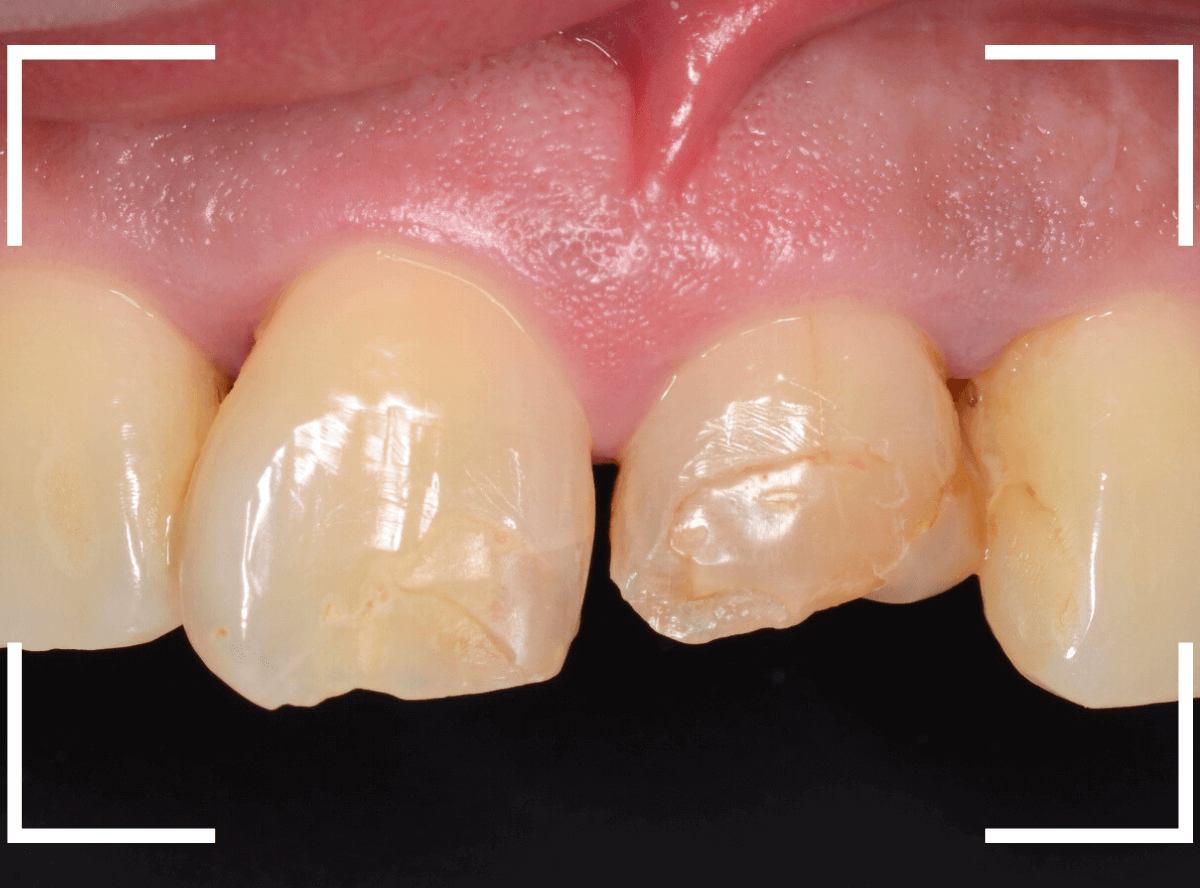

Case.1 下に下がってしまった上前歯のセラミックのやり替えの治療

今回は、上の前歯のセラミックの形が気になるので、大分時間も経っているので新規に作り直したいというご希望の患者さんのお話です。

たしかに、隣の歯に比べてかなり下に下がってしまっています。

治療した時の状況がわからないので、治療時からどれくらい下がったのかは正確にはわかりません(><)

裏側を見ると少し歯肉が腫れています。

歯周病の治療と並行して、セラミックの作り直しをすることになりました。